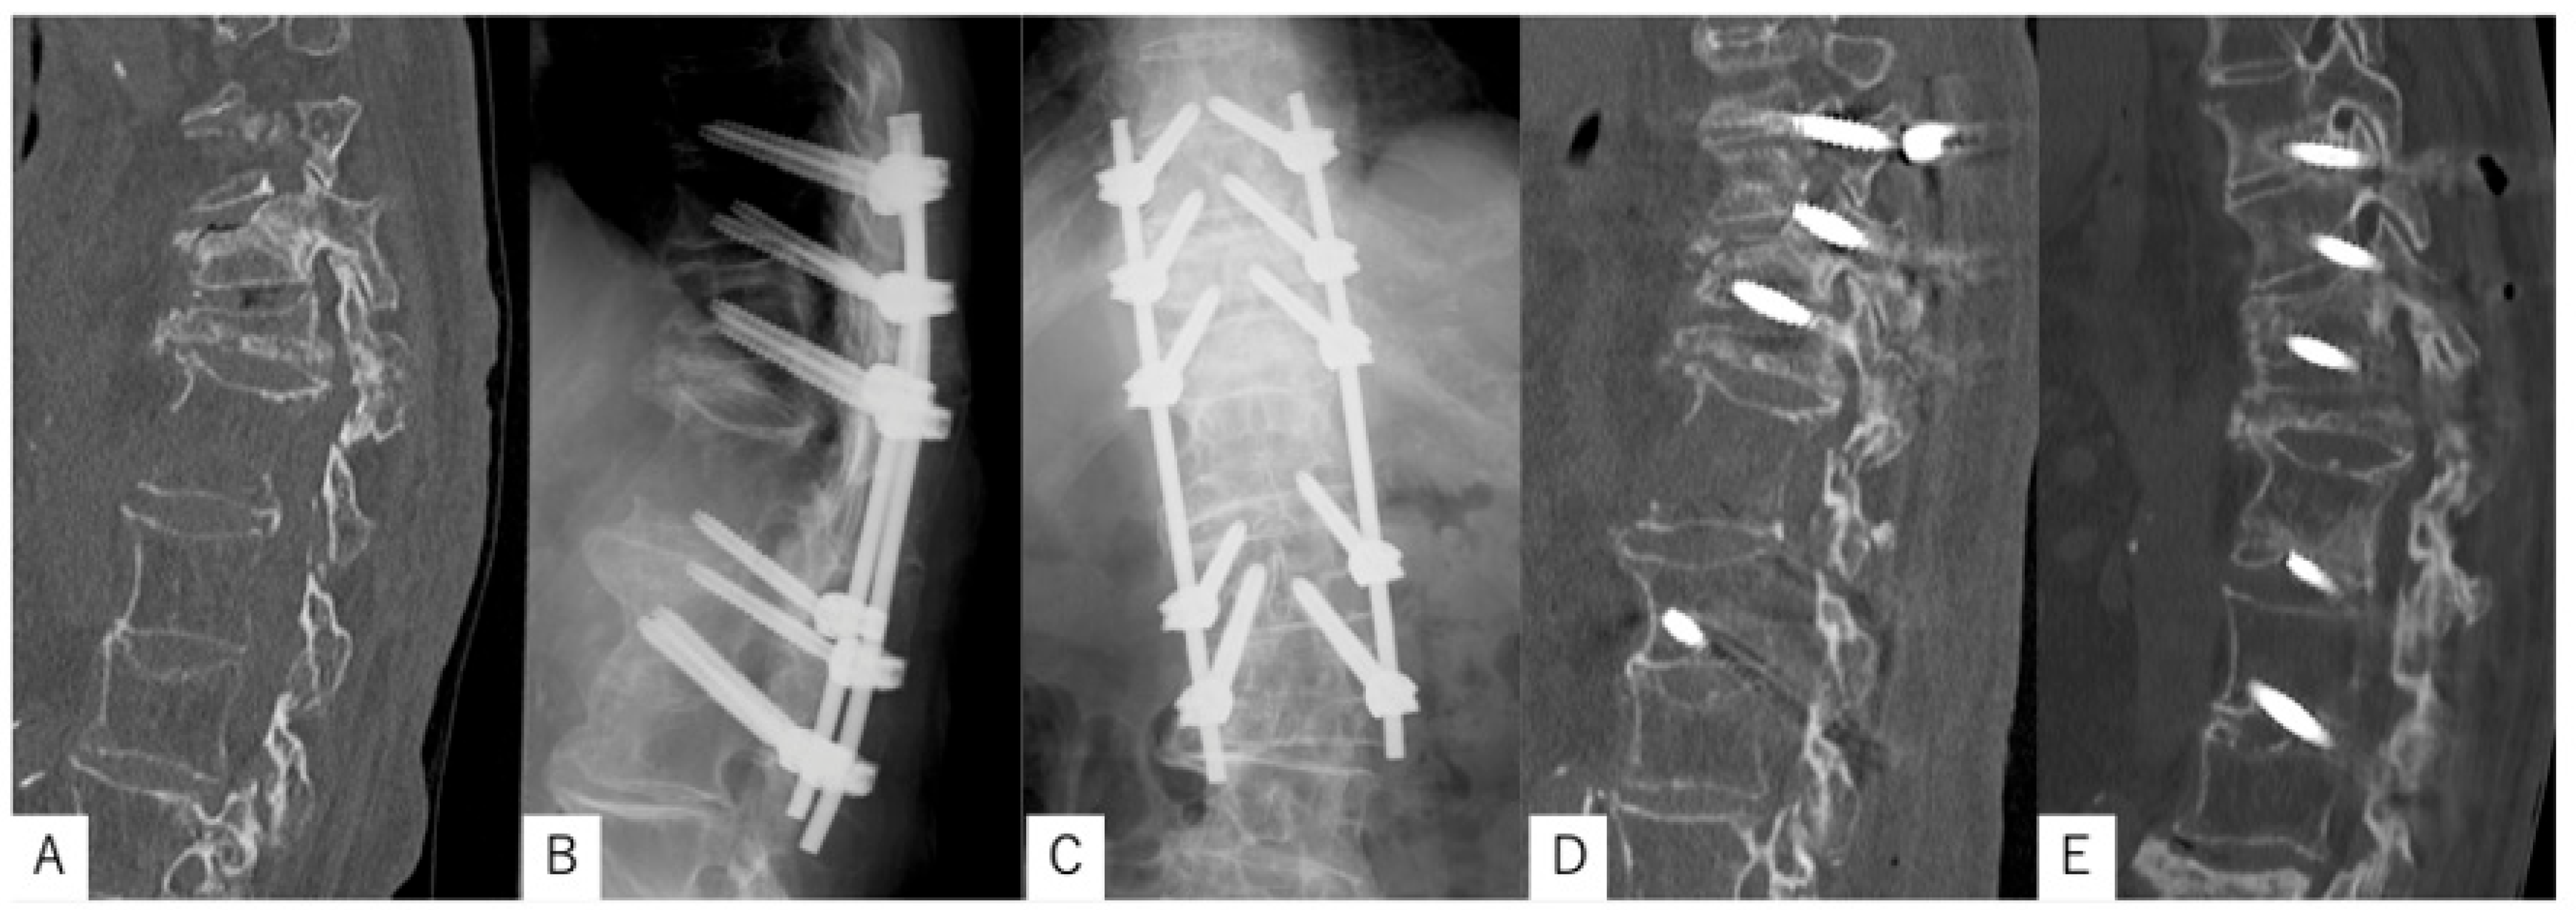

3.1. Case Presentation 1

3.2. Case Presentation 2